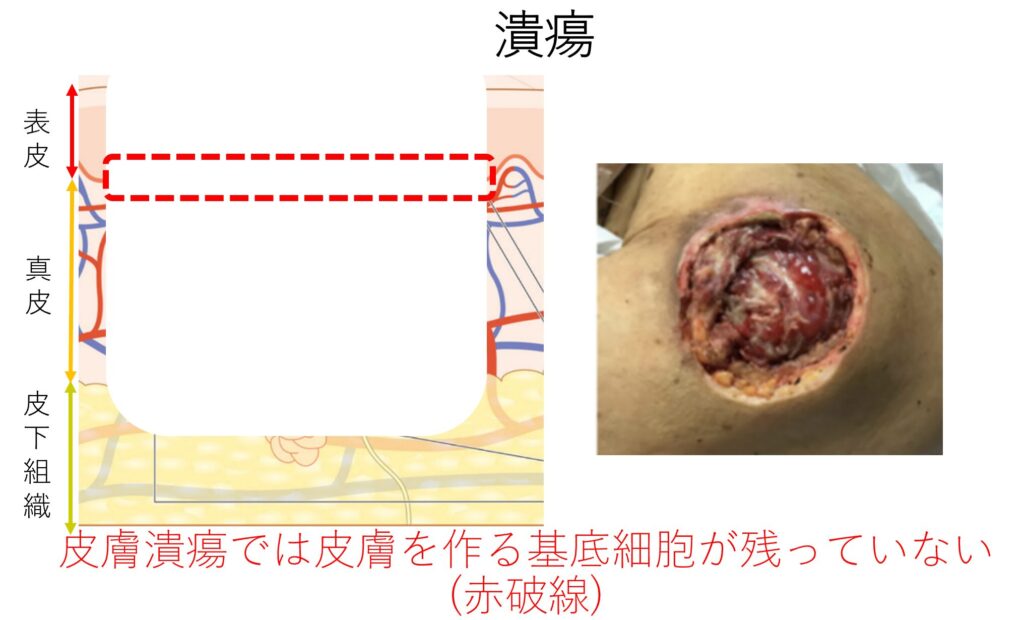

実践します!褥瘡ケア「いつもの方法を見直してみよう」エール在宅診療所。

実践します!褥瘡ケア「いつもの方法を見直してみよう」エール在宅診療所。

実践します!褥瘡ケア「いつもの方法を見直してみよう」エール在宅診療所。